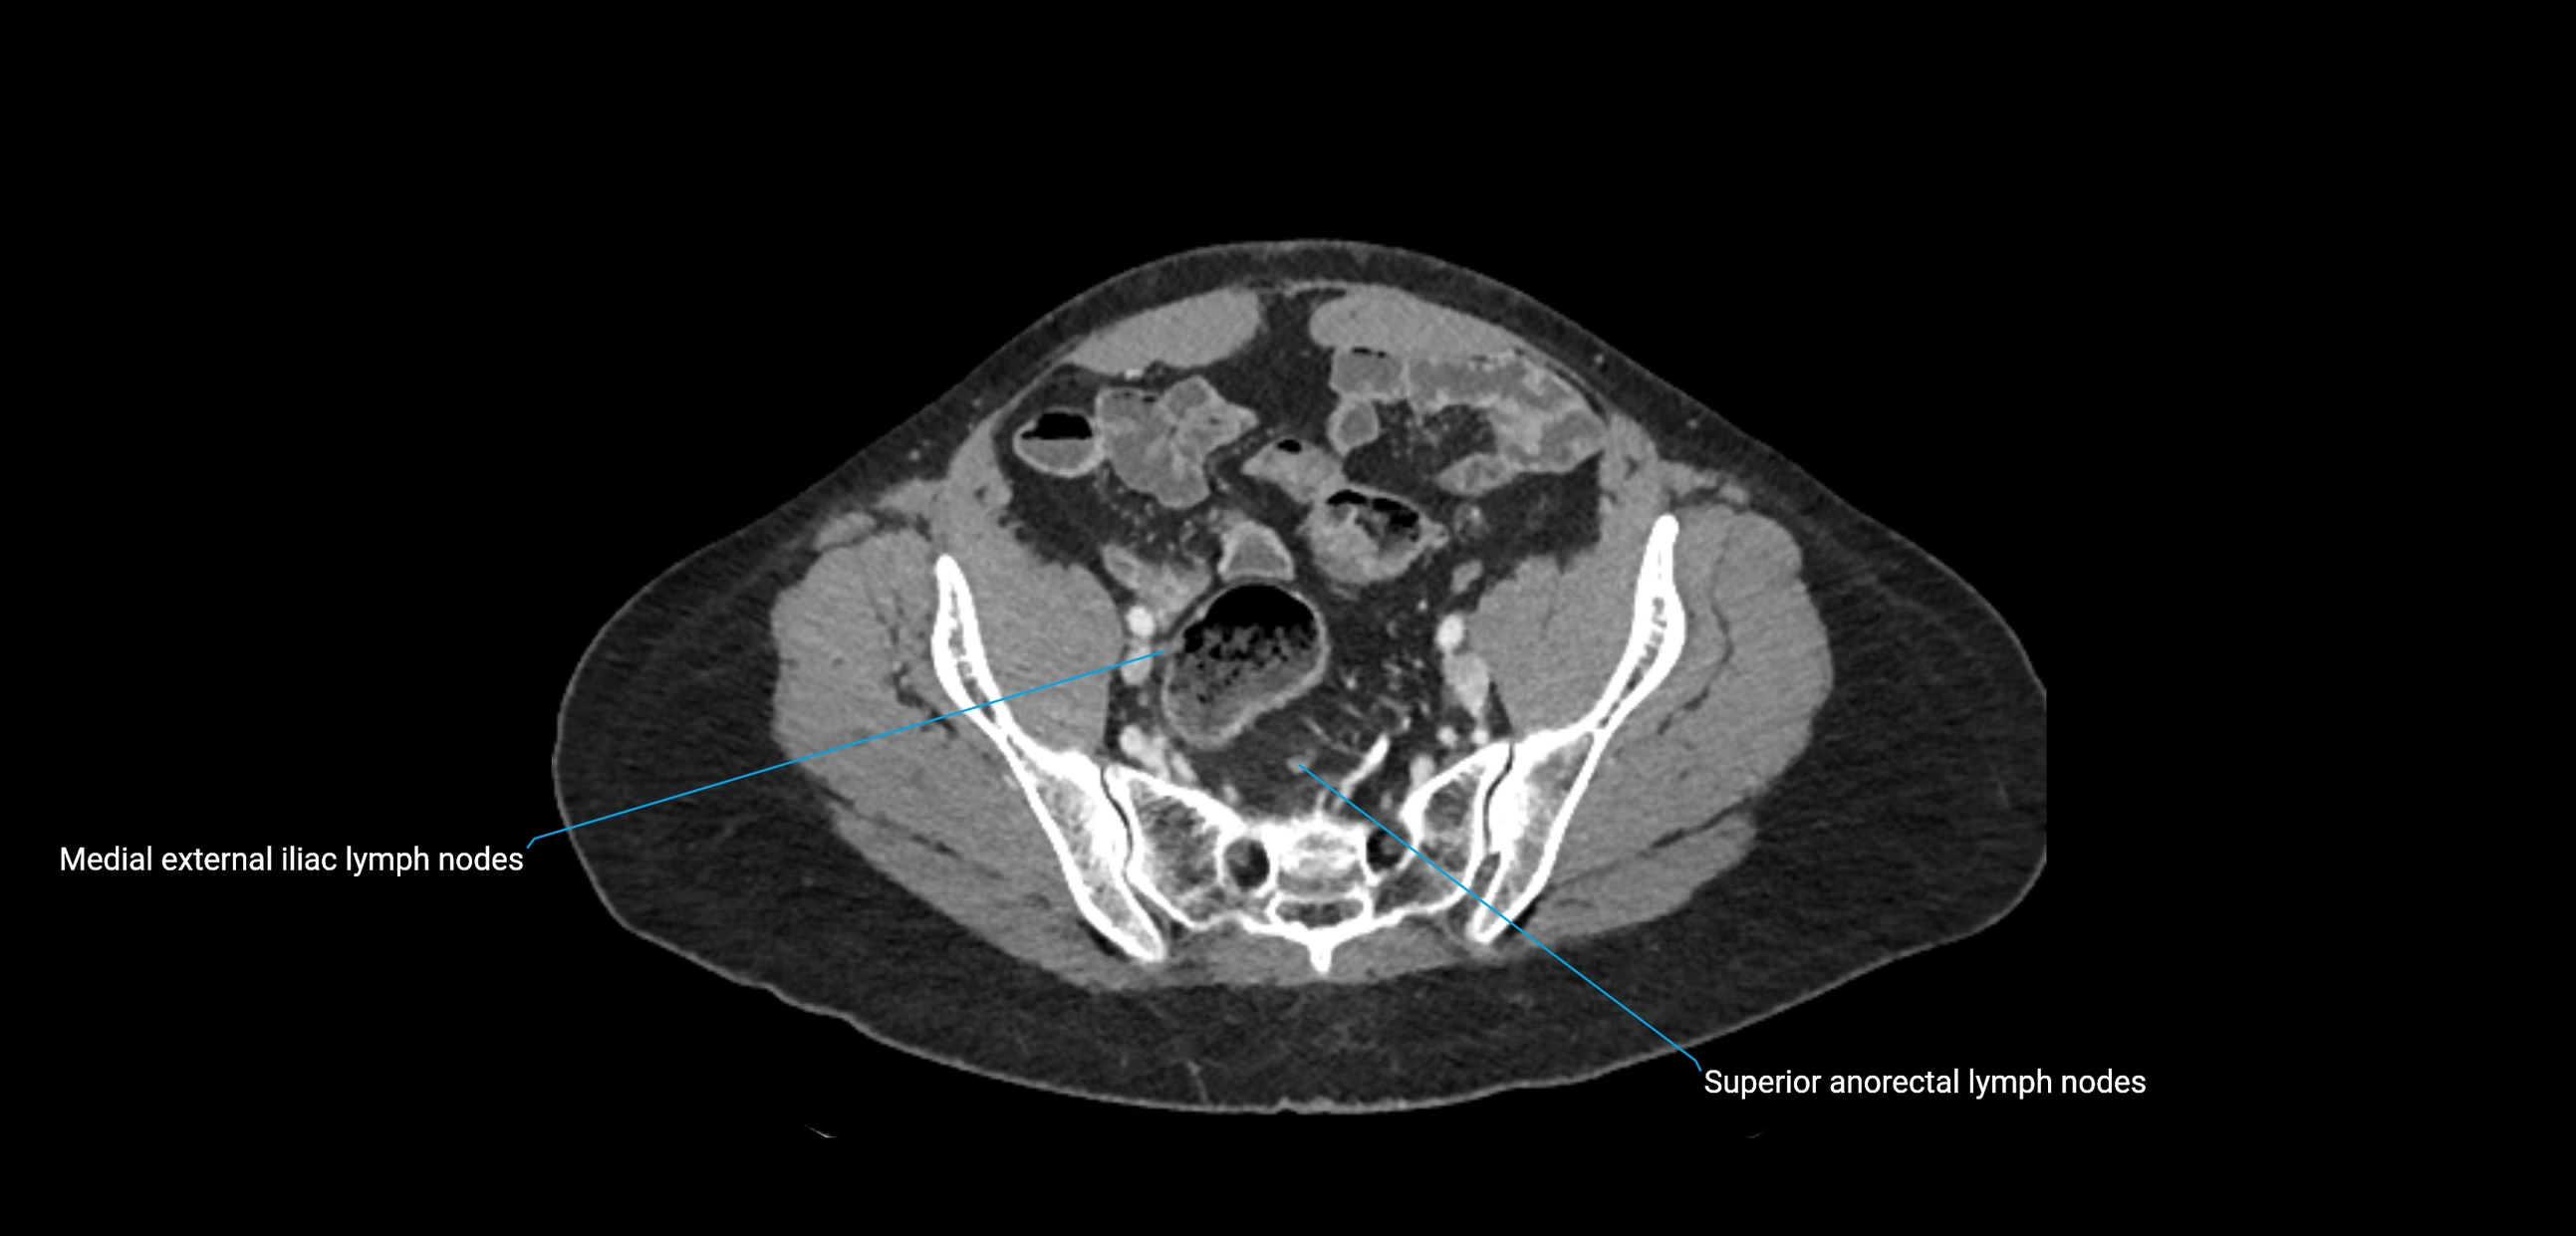

CT Appearance

CT Pre-Contrast:

• Nodes appear as soft-tissue density nodules adjacent to the aorta and IVC

CT Post-Contrast:

• Normal nodes enhance homogeneously

• Malignant nodes may show heterogeneous enhancement, central necrosis, or conglomerate formation

• Size >1 cm short axis is suspicious, though morphology and distribution are equally important